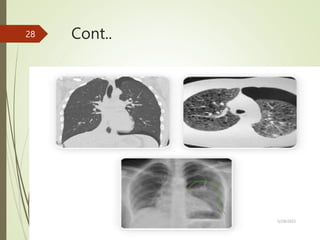

3 CT imaging

 determine underlying cause in context of trauma &

concurrent injuries

 Findings –air in the space , can evaluate the location ,

pleural pathology & lung disease

Cont..

5/29/2023

28